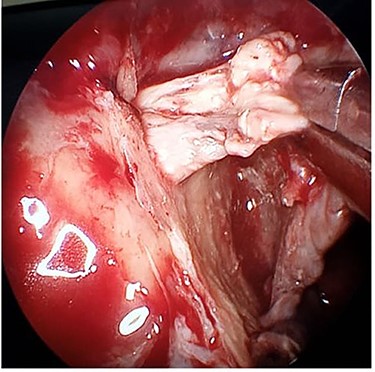

After multidisciplinary discussion, he was taken to the theatre the following day where he underwent right ethmoidectomy, uncinectomy and wide middle meatal antrostomy. The right sphenopalatine artery was found thrombosed (Fig. 4). This was combined with transoral resection of the right palatine process of maxilla. A sample of the discharge was sent for bacteriologic and fungal smear and culture. Immediate palatal reconstruction was performed using a temporary obturator which was replaced 2 weeks later by a permanent one. The smear was negative for both bacterial and fungal elements, and no growth was reported in the culture. The patient’s general condition improved and was discharged 4 days later.

Intraoperative endoscopic image of the thrombosed right sphenopalatine artery.

COVID-19 has been shown to be a multi-systemic disease rather than just a respiratory system infection. One of its main pathophysiological mechanisms is the occurrence of a generalized pro-thrombotic state with resultant microvascular and macrovascular thromboembolism. Han et al. noted that coagulation parameters such as raised D-dimers, fibrin degradation products and fibrinogen correlate with the severity of COVID-19 infection. Also, these parameters were noted to be elevated in milder forms of the disease compared with healthy controls [3]. The mechanism of thrombophilia in SARS-CoV-2 infection is not fully elucidated; however, some putative mechanisms were proposed, including a pro-coagulable cytokine storm, viral tropism for angiotensin converting enzyme 2 (ACE2) receptors in vascular endothelium and raised antiphospholipid antibodies. Reports of pulmonary embolisms, deep vein thrombosis, cerebral infarction and cerebral venous sinus thrombosis associating COVID-19 infection are increasing in recent literature [4]. In our patient, we have found the right sphenopalatine artery completely thrombosed intraoperatively, and we presume that the right internal maxillary artery, its descending palatine branch or both have also been thrombosed explaining the patient’s extensive hard palate necrosis.